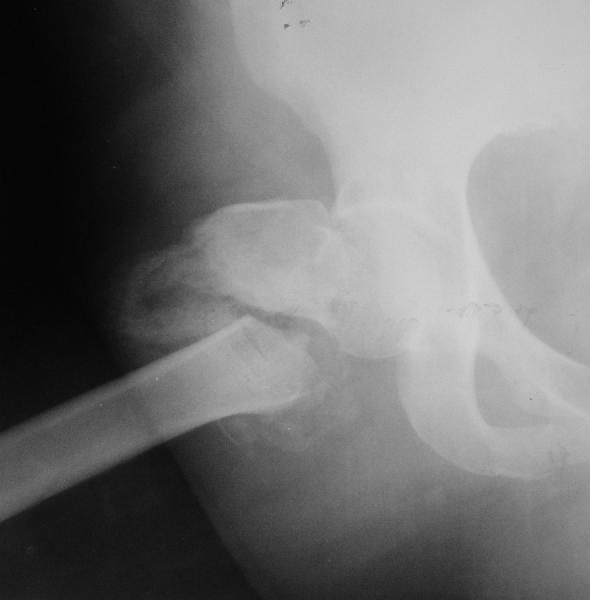

Относительно молодая женщина(39 лет), поступила в клинику в марте 2005 года, через 3 месяца после травмы с Неправильно срастающимся поперечным межвертельным переломом правого бедра. Был выполнен закрытый интрамедуллярный остеосинтез правого бедра канальным реконструкционным стержнем ChM. Ожидали бОльших проблем на операции, результату обрадовались. Как оказалось, зря. Сращение наступило через 3,5 месяца после операции.

В ноябре 2005 года произошел перелом шейки бедра и винтов в ней. В апреле 2006 импланты были удалены. В приложении фото и рентгенограммы больной. Сопутствует ожирение 4 ст. (при росте 168 см., вес больной 140кг.), сахарный диабет II тип. Имеется медиальная неустойчивость коленного и голеностопного суставов, при нагрузке колено вальгируется на 15-20 градусов.